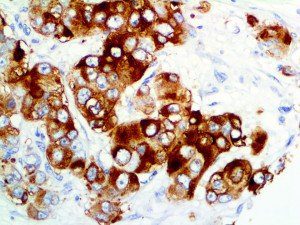

The first cytokines released are interleukin 1β (IL-1β) and tumor necrosis factor-α (TNF-α), which attract a variety of circulating white blood cells (WBCs) to the infection site, including neutrophils, monocytes, macrophages, and natural killer (NK) cells. This response, along with the antipathogenic chemicals released by these cells (i.e., complement), comprise the innate immune response. These cells directly attack the invading pathogen and also release additional cytokines, chief among them interleukin-1 and 6 (IL-6). IL-6 is essential for invoking the adaptive immune response, which calls T-cells, B-cells, and T helper (Th) cells to the infection site. IL-6 also stimulates further recruitment, proliferation and activation of macrophages.

This activation induces inflammatory monocytes to highly express IL-6, starting a localized and then systemic cascade effect that results in hyperproduction of IL-6, which accelerates the inflammatory process. Because IL-6 also increases vascular permeability, excessive levels cause blood vessels to become very leaky. This, along with clotting factors released from vascular endothelial cells, stimulates the coagulation cascade, resulting in microthrombosis (tiny clots), which leads to ischemia and tissue death of the kidney, intestines, heart, liver, brain and extremities.